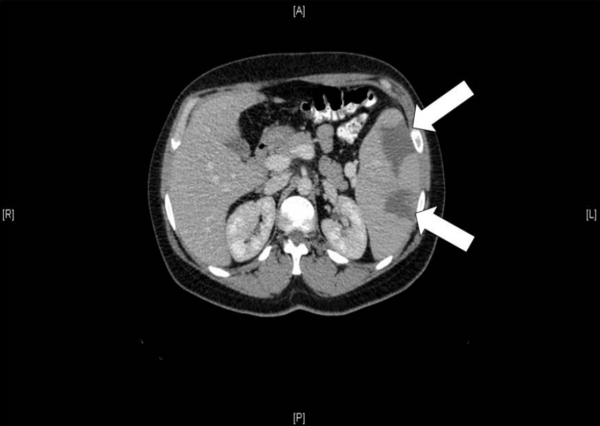

В кишечнике развивается геморрагический инфаркт. Он часто осложняется гангреной кишечника, прободением стенки кишки и перитонитом[5].